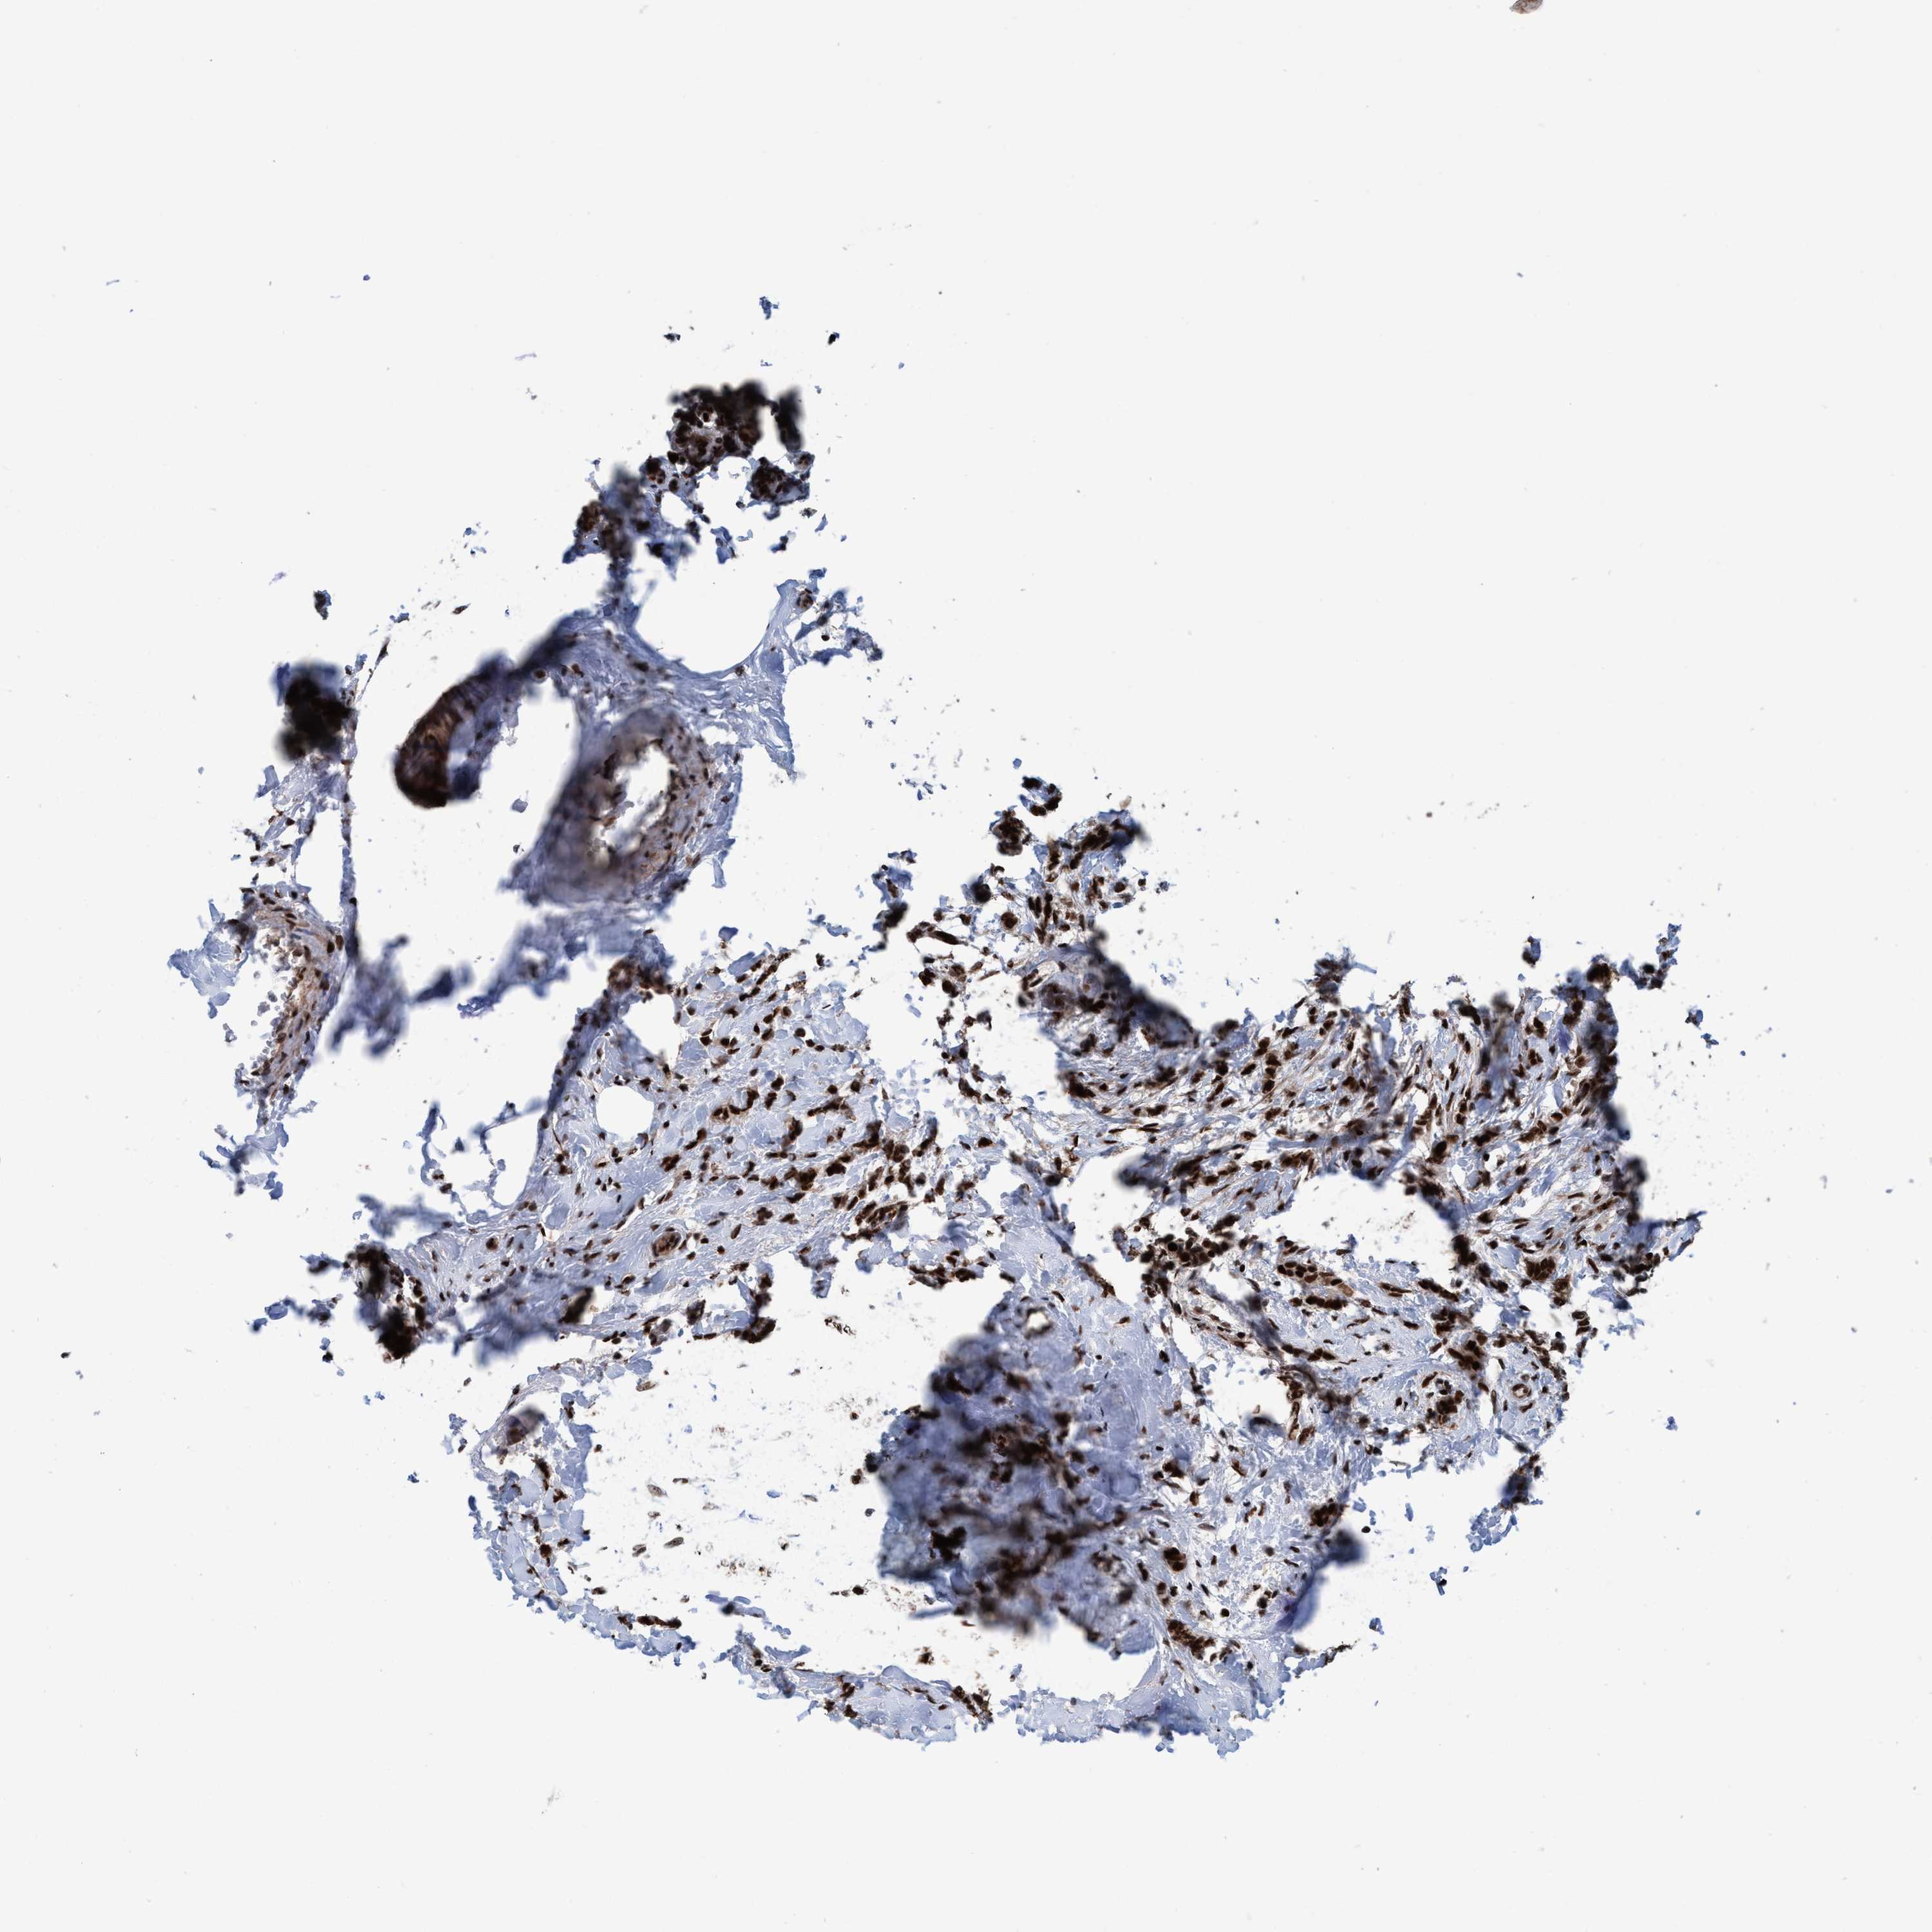

BRCA TCGA BRCA VALIDATION PROTEIN EXPRESSION